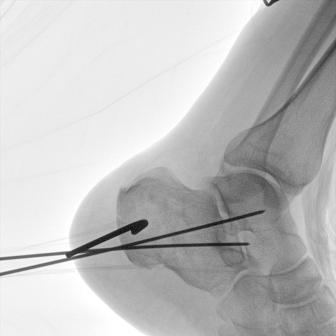

Clinical picture

臨床圖片